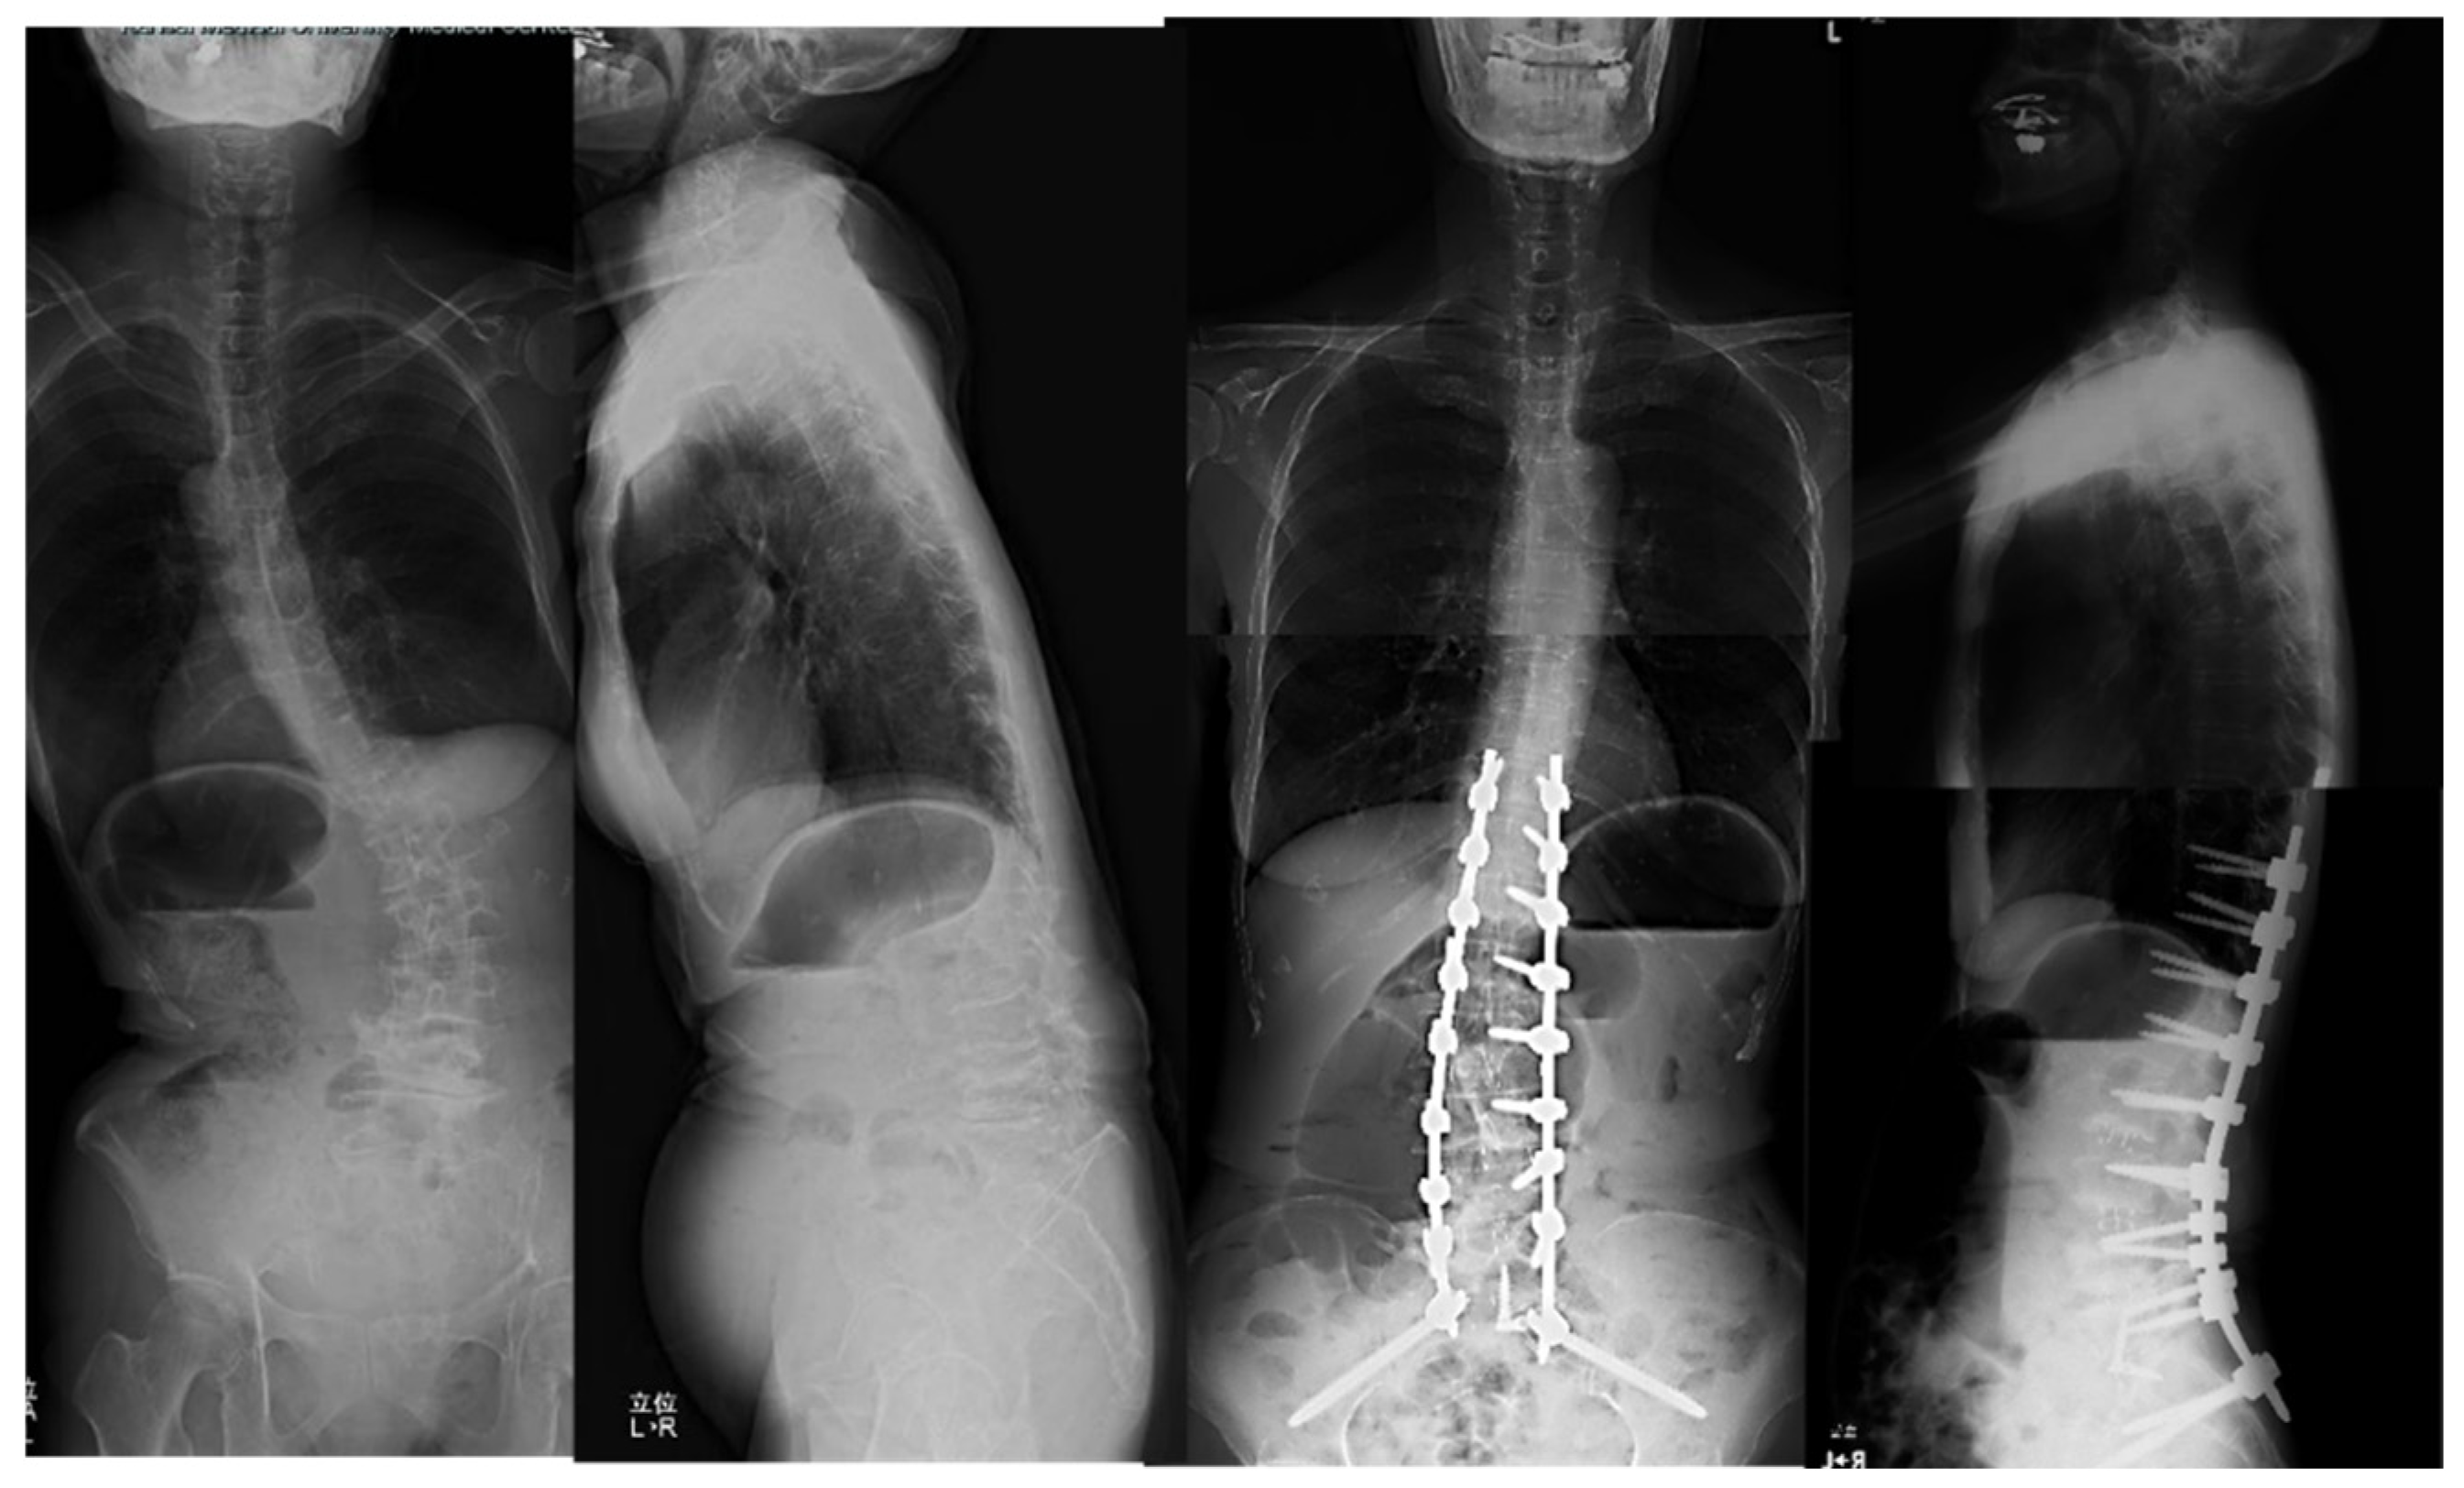

Case 1: 78 years old, female, Degenerative lumbar scoliosis

The patient complained of severe low back pain, difficulty of standing, and pain and numbness in lower extremities preoperatively. She received cMIS employing OLIF51 with an intraoperative estimated blood loss of 294ml and operation time of 418 mins totally. The lumbar lordosis increased four to 54 degrees postoperatively and PI-LL mismatch became zero degree postoperatively (Figure 5).

Figure 5. 78 years old female, degenerative lumbar scoliosis. The successful cMIS with OLIF51 was performed with a total blood loss of 294ml.

LL was corrected to 54 degrees from four degrees and PI-LL mismatch became zero at follow-up.